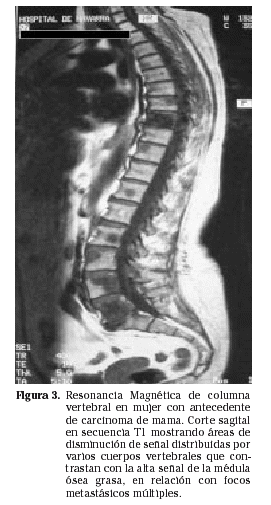

La Resonancia Magnética (RM) ha mostrado su eficacia en dos aspectos: es el método más seguro para evaluar la extensión en hueso medular de una metástasis y es la mejor técnica para delimitar la extensión a partes blandas y su relación con estructuras neurovasculares y tejidos adyacentes. La extensión intramedular se visualiza en las secuencias T1, mediante cortes coronales y sagitales, debido a que el tumor da una baja intensidad de señal en contraste con la alta señal normal de la médula ósea grasa (Fig. 3). La lesión extraósea se evalúa en la secuencia T2 mediante cortes axiales, en los que en condiciones normales la masa muscular que rodea al hueso es de baja intensidad de señal y el tumor es de alta señal, permitiendo una buena diferenciación entre uno y otro14.